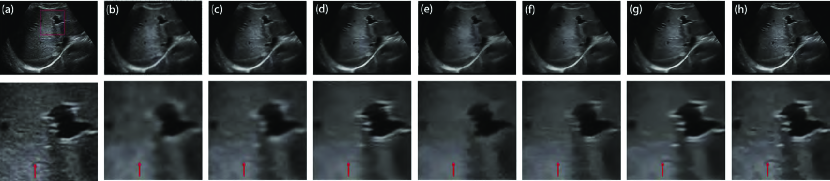

The parameter is an important parameter that is related to the noise level estimation. Noise level estimation is a prerequisite for various detail-preserving image denoising methods [21] but has remained as an unsolved challenging problem in ultrasound image despeckling. According to (16), if is set to a large value, a large diffusion coefficient is obtained that will cause some details to be damaged after speckle reduction. However, if is set to a small value, a small diffusion coefficient is achieved that will increase computational costs in the despeckling process. To explore the impact of parameter , we set with different values. Fig. 4 depicts the despeckled results of different . It is observed that there is a significant level of noise in the despeckled result of . As indicated by the red arrow in Fig. 4(d), the meaningful detail is damaged after noise removal in the case of . Our method achieves not only satisfactory feature preservation but also desirable noise reduction in the case of . In real image experiments, we find that the best range of is from to . Here, we set as .